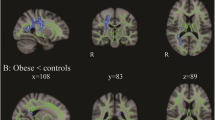

The VBM meta-analysis revealed significant reductions in both the left hippocampus (cluster size 7224 mm3, subregion volume 7224 mm3, MNI coordinates (−32, −6, −26), z = 2.67, p = 0.0076) and right hippocampus (cluster size 7296 mm3, subregion volume 7296 mm3, MNI coordinates (26, −6, −26), z = 2.67, p = 0.0076) compared to healthy controls (Fig. 4).

VBM meta-analysis map of T2DM (axial, sagittal and transverse cerebral views are presented, overlaid on MNI template). Red areas are statistically significant results (P < 0.05 FDR corrected). Significant reductions were found in left hippocampus (MNI coordinates (−32, −6, −26), z = 2.67) and right hippocampus (MNI coordinates (26, −6, −26), z = 2.67) in T2DM compared to controls